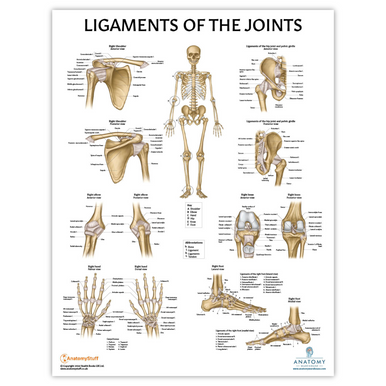

In addition to the information above, here is a curated collection of images related to Ligaments Meaning Types Functions Anatomy Example More.

- Back Talk Systems, Colorado » Ligaments Of The Joints Anatomical Chart